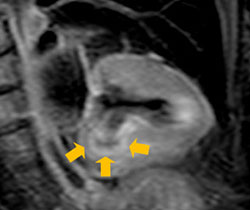

• 図2:T2強調画像:心サルコイドーシスの症例

左室心筋下壁に心筋浮腫が疑われる

(黄色矢印部位の高信号域・白色部位)。